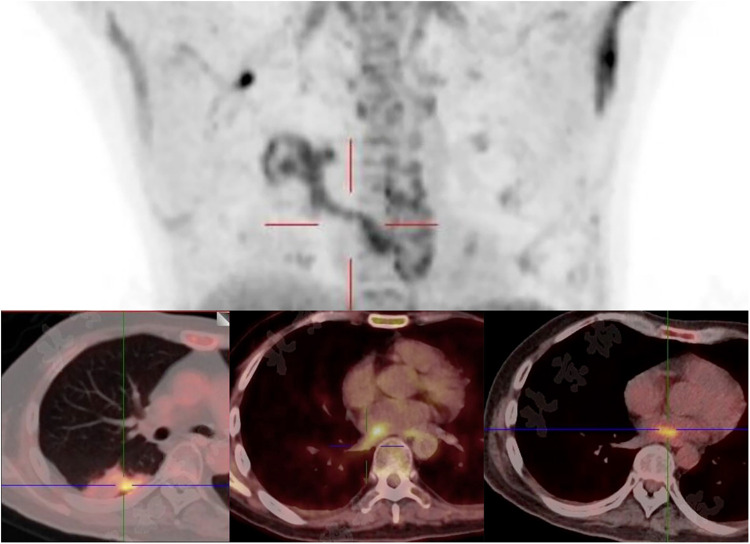

Volvariella volvacea (V. volvacea), an edible mushroom, may act as a pathogenic agent causing invasive fungal infections (IFIs) in immunocompromised patients. We present a 38-year-old male with persistent high fever post-allo-HSCT. Plasma mNGS revealed rising V. volvacea DNA loads (1,137 copies/μl). Intravenous antifungal therapy was initiated upon the diagnosis of IFI. Transthoracic echocardiography showed a 4 × 1 cm left atrial vegetation, with enhanced CT confirming multiorgan septic emboli (brain and kidney). PET/CT revealed a left atrial vegetation originating from a right lung infectious lesion, spreading contiguously into the left atrium via the pulmonary vein. Urgent vegetation resection was performed, followed by continued intravenous antifungal treatment. At the 5-month follow-up, the patient was afebrile with negative mNGS, completely resolved pulmonary lesion, and an improved quality of life. This case highlights the potential value of surgical-targeted antifungal therapy for fungal endocarditis and suggests practical principles: including mNGS-guided diagnosis, urgent surgical excision, long-term optimized antifungal therapy, and regular follow-up surveillance of the residual infected lesion.